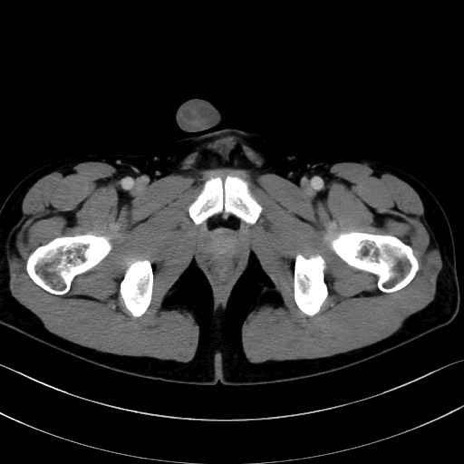

長内転筋(Adductor longus muscle)のCT画像の解剖

長内転筋 (Adductor longus)

短内転筋 (Adductor brevis)

大内転筋・小内転筋 (Adductor magnus / Adductor minimus)